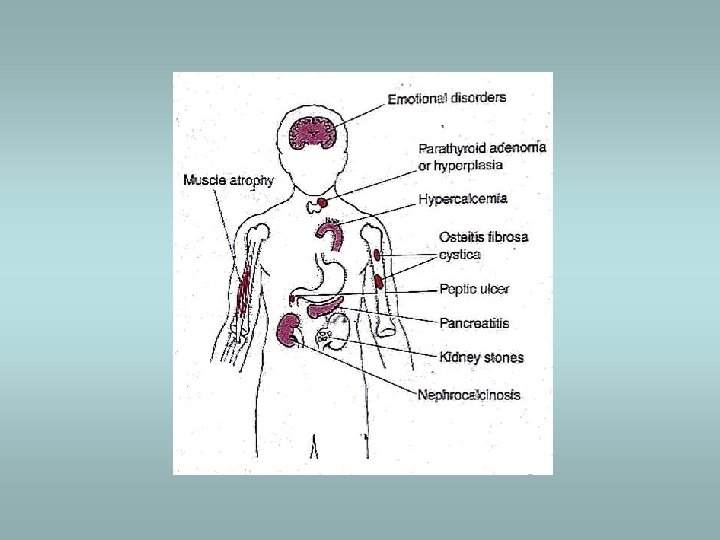

Parathyroid gland Primary hyperparathyroidism ü Hypersecretion of parathormone ü Caused by adenoma (80%), hyperplasia (15%), carcinoma (5%) ü Bone resorption, hypercalcemia – osteoporosis, muscle weaknes, nephrolithiasis, ulcers, pancreatitis, headache, depression Secondary hyperparathyroidism ü In patients with renal failure ü Compensatory hypersecretion of parathormone (reaction to phosphate retention and hypocalcemia)

Parathyroid gland - tumors Adenoma ü Solitary, encapsulated – compression of adjacent gland ü No stromal fat ü Composed predominatly of chief cells ü Part of MEN I, MEN II Carcinoma ü Rare ü Invasion, metastases Hyperplasia ü All glands ü Fat cells interspersed